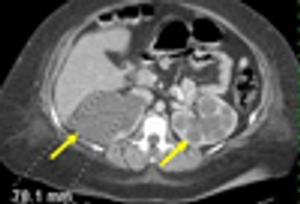

Autosomal dominant polycystic kidney disease (ADPKD) is common. Presenting symtpoms include hypertension, hematuria, proteinuria, and renal insufficiency.